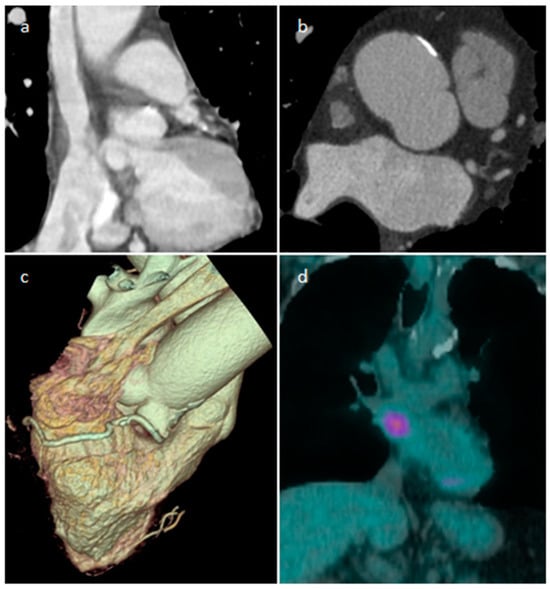

| Paraganglioma | Adulthood | On the roof of left atrium, right atrioventricular groove | elevated blood pressure and severe headaches | “salt and pepper” appearance, highly vascular, parasitizes blood supply from coronary arteries, elevated serum metanephrines Malignant up to 25% | Solid heterogeneous echogenic mass with clear boundaries, and detectable blood flow signals inside it in the color Doppler | A mass of soft-tissue density with homogeneous (smaller lesions) or peripheral (larger lesions with hemorrhage, necrosis and cystic degeneration) enhancement | Iso-hypo T1w, hyper T2w, peripheral LGE. Perfusion imaging shows strong enhancement |

- Carvalho, J.G.; Gho, J.M.I.H.; Budde, R.P.J.; Hofland, J.; Hirsch, A. Multimodality Imaging of Cardiac Paragangliomas. Radiol. Cardiothorac. Imaging 2023, 5, e230049. [Google Scholar] [CrossRef]